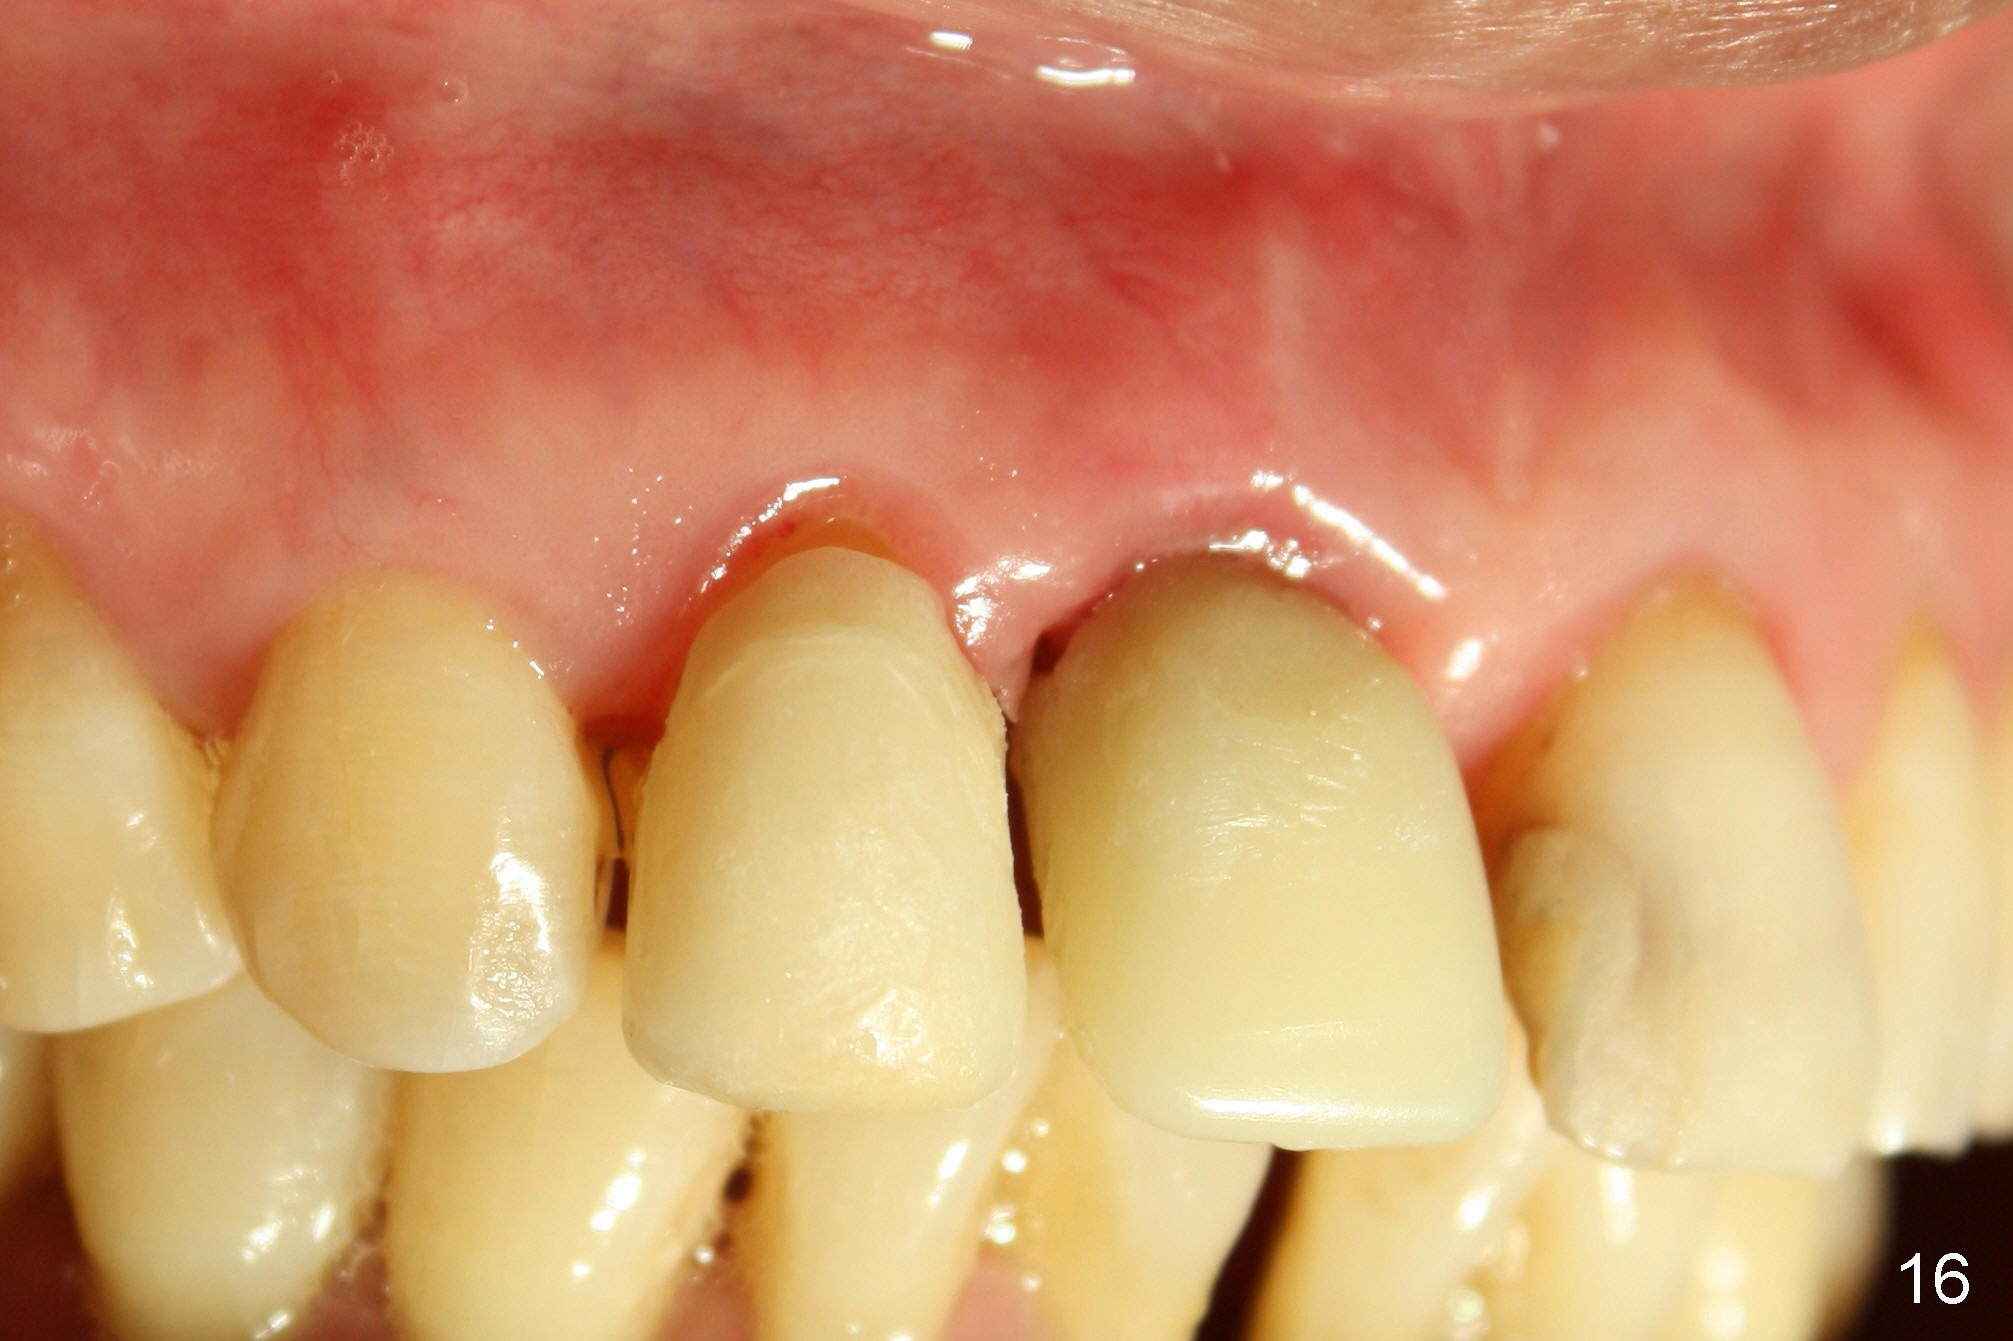

A 64-year-old lady requests replacing #7 and 8 crowns (Fig.1,2). When #8 is extracted, the labial plate is found to be missing (Fig.3). Following 2 mm pilot drill (Fig.4,5 P), 3.8 mm tap drill (Fig.6,7 T) and 4.5x14 mm implant (Fig.8 I) and 4.8 mm abutment (Fig.9 A), corticocancellous bone is harvested from the left tuberosity and placed in the labial gap of the socket (Fig.10 G). Collagen dressing is placed over the bone graft (Fig.11 C). The former is secured in place by an immediate provisional (P).

Four-month follow up shows that bone graft from the tuberosity appears to have healed with the implant microthreads (Fig.17 *); there is a diastema between #8 and 9 (arrowheads). Before removal of the provisionals of #7 and 8 for final impression, new composite is added to the mesial surface of #9 as the first step of closure of the diastema (Fig.18 <).